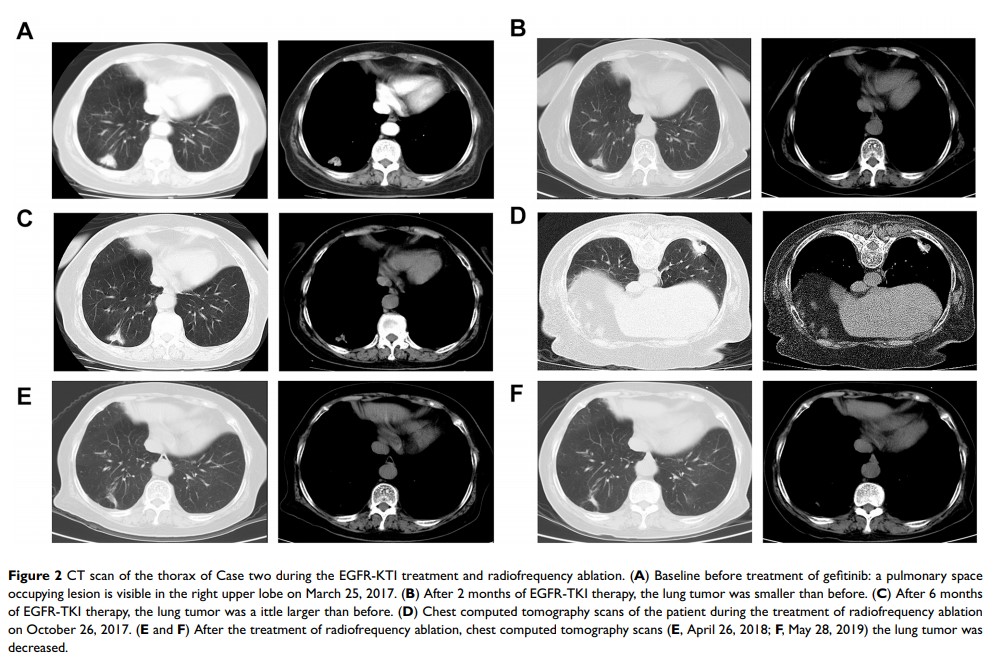

对于具有 EGFR 酪氨酸激酶抑制剂获得性耐药的 EGFR 突变晚期肺癌,射频消融和持续的 EGFR 酪氨酸激酶抑制剂治疗可延长疾病控制:两个病例报告